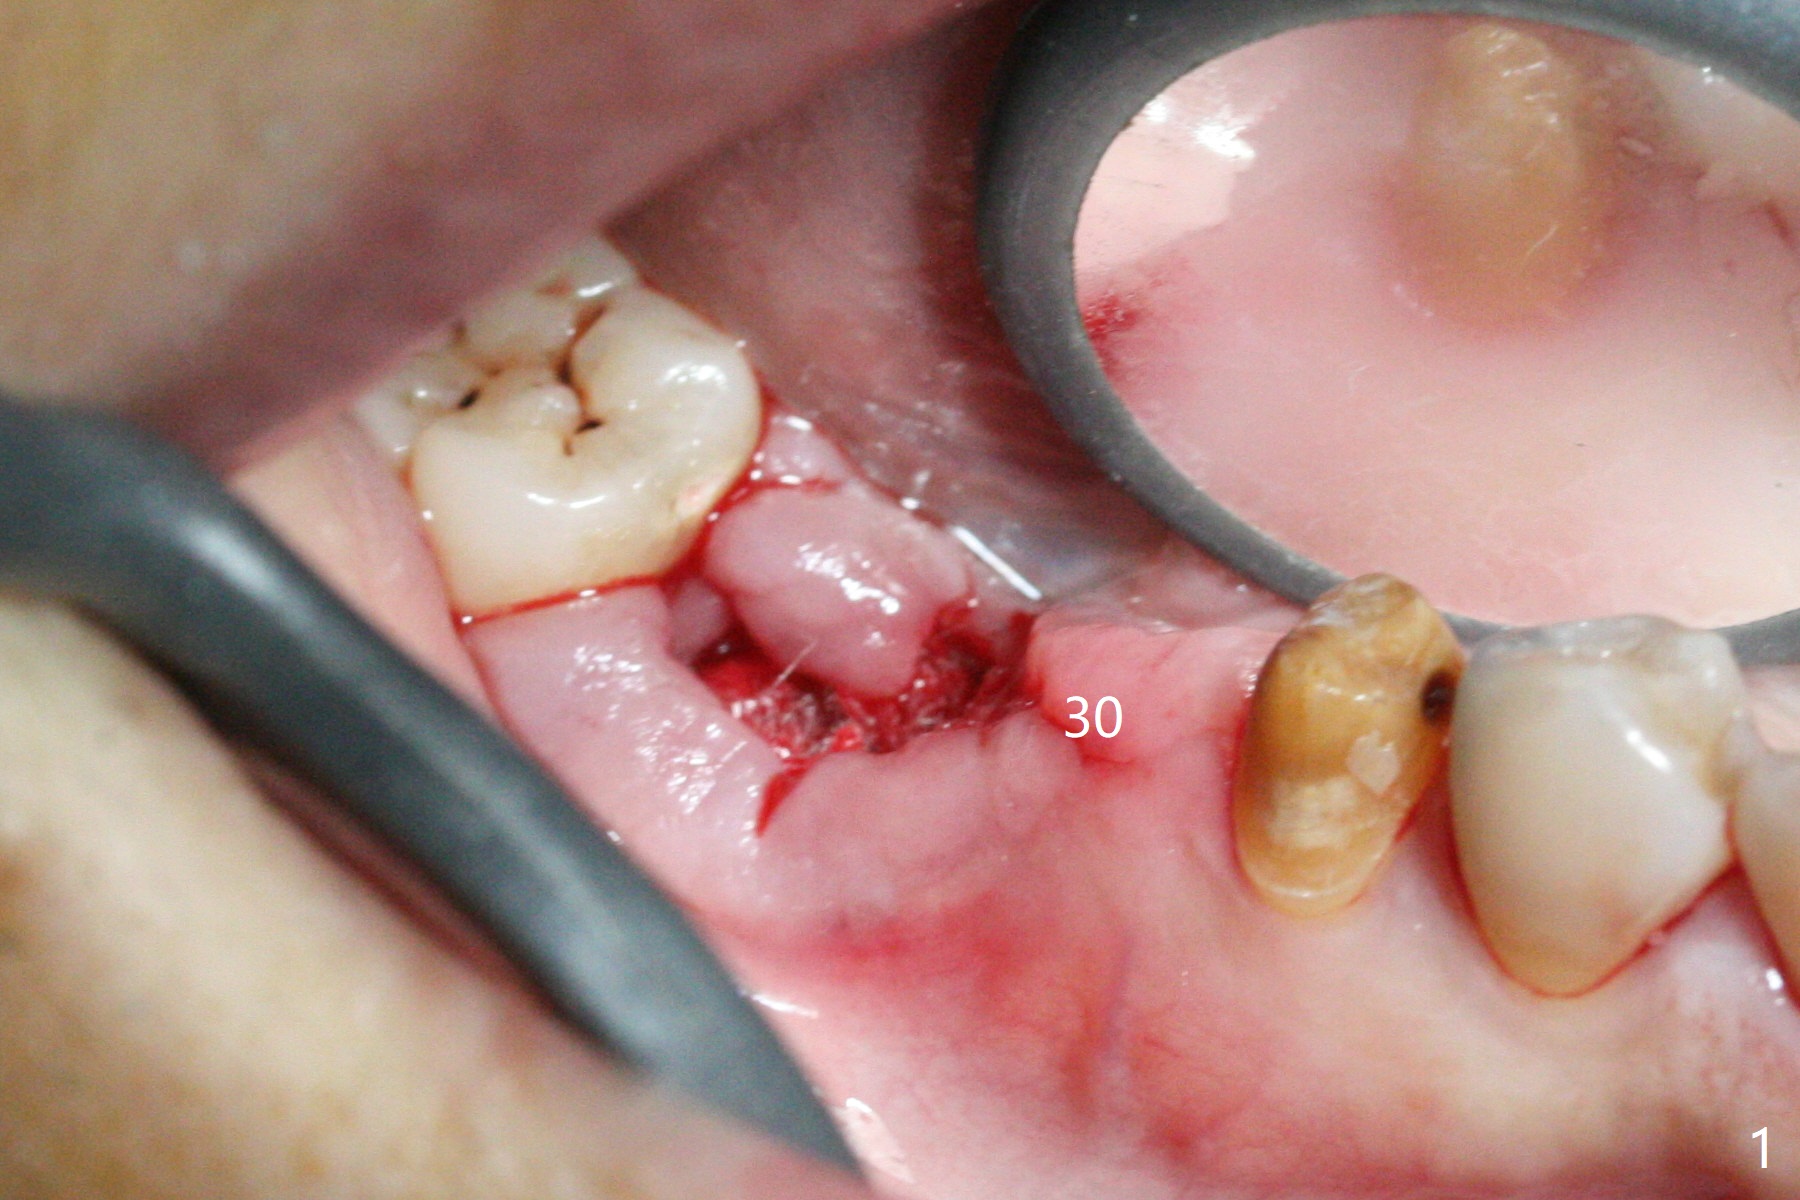

The edentulous area at #30 looks narrow after #31 extraction (Fig.1) and after incision (Fig.2). As planned, osteotomy is established at #30 as a premolar and at the mesial slope of #31 socket (Fig.3). Following adjustment of the trajectory at #30 and sequential osteotomy until 3.5x11.5 mm, two of 4x10 mm dummy implants are inserted with stability as well as dummy abutments (Fig.4). Final implants are 4x11.5 mm with insertion torque > 50 Ncm; after suturing, abutment margins are subgingival, particularly at #31 (Fig.5 (*: Vera Graft)). Periodontal dressing is applied. Provisional will be fabricated when the wound heals. It appears that the small and regular implants are appropriate for the narrow mesiodistal space at #30 and 31. There appears to be bone growth around the implants nearly 4 months postop (Fig.6).